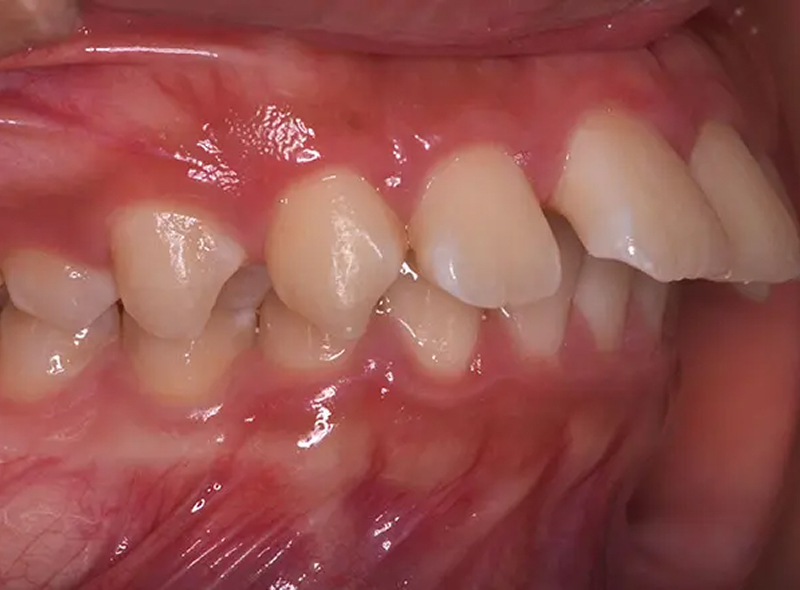

Case02凸凹と出っ歯を改善した症例

海外からの転医の患者さんです。日本で留学することになったので、治療の続きをしたいとのことでした。既に両側上顎第1小臼歯2本が抜歯されていました。上顎前歯は著しく前方に傾斜しており、審美的に大きな問題がありました。この状態からの治療計画なので、制限がありましたが、無事、上顎前歯を後方に移動し、前歯を噛ませて、素敵なスマイルを獲得できました。

| 主訴 | 凸凹と出っ歯を治したい |

|---|---|

| 診断 | 両側アングル2級の上顎前突 |

| 矯正方法 | 上顎第1小臼歯2本抜歯を伴うマルチブラケット |

| 矯正期間 | 18か月・20回 |

| 費用 | 730,000円(税別) |

| 調整料 | 月1回 5,000円(税別) |